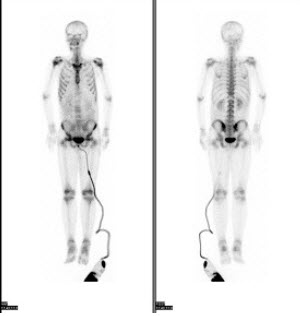

男,21岁,临床诊断胃癌,诉全身多处骨关节疼痛,行全身骨显像如图,对此影像下列描述正确的是( )

A:胸12椎体放射性“冷区”

B:若同时X线检查为阴性则提示骨转移可能性大

C:“冷区”的出现一定表明骨转移

D:患者胸骨浓聚提示骨转移

E:胸12椎体可能存在肿瘤的骨髓浸润